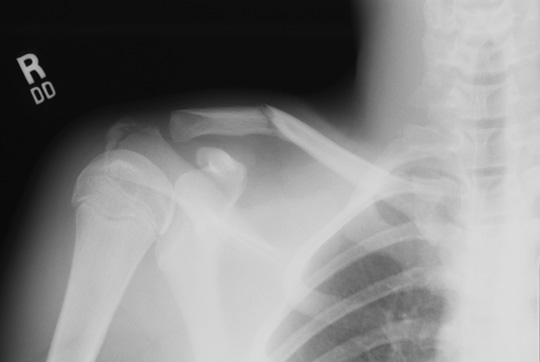

| This radiograph of the shoulder region reveal a fracture in the midportion of the right clavicle in a young boy. This was treated with a splint. In children, healing of fractures is very complete, with remodelling that leaves little evidence for prior fracture. |